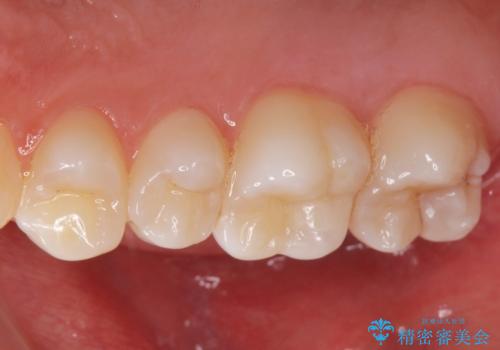

歯と歯の間の虫歯 e-maxインレーで修復

- 歯と歯の間に虫歯が見られたために、拡大鏡下でう蝕を取り除き、e-maxインレーで治療しました。

- e-maxインレー 7.7万円 費用は治療当時の料金となります